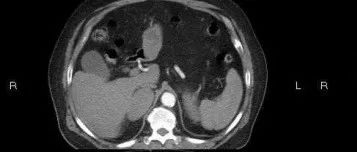

老年男性,左侧腰部疼痛酸胀1月,请诊断!

医学影像  yxyx-app  医学影像APP,打造伴随医生快速成长的影像学习社区。与影像园(Xctmr.com)一起提供最全面的影像案例库、基础(解剖、病理、影像诊断)知识、影像技术及考题等,为医生提供最佳的医学影像参考。【所属科室】泌尿外科【基本资料】患者,男,65岁【主诉】左侧腰部疼痛酸胀1月【现病史】患者于1月余前无明显诱因下出现左侧腰部疼痛酸胀伴头晕,无恶心呕吐,不伴肉眼血尿。...